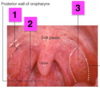

Identify 1

Soft Palate

Identify 2

Vallecula

Identify 3

Epiglottis

Identify 4

Piriform fossa

Identify 5

Pharyngo-Oesophageal Junction

Identify 1

Palatoglossal Fold

Identify 2

Palatopharyngeal Fold

Identify 3

Tonsillar Fossa ( & Palatine Tonsil)